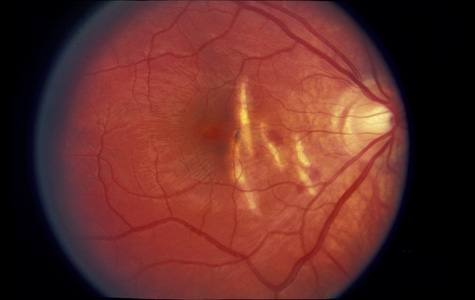

The visual acuity in commotio retinae varies from 20/20 to 20/400 and does not always correlate with the degree of retinal opacification. There is no known treatment. The prognosis is usually excellent except in cases with associated subfoveolar choroidal rupture and in cases with choroidal rupture with subfoveolar hemorrhage. Poor visual recovery can also be expected in cases with severe retinal pigment epithelial damage. Serous retinal detachment (Fig. 11) signals this condition, which can be confirmed by leakage of fluorescein into the subretinal space.70

Fig. 11. A: Serous detachment of the macula and intraretinal and vitreous hemorrhage after the eye was struck with a baseball. B: Three months later. The hemorrhages have cleared, revealing severe pigment epithelial necrosis. The visual acuity is counting fingers.